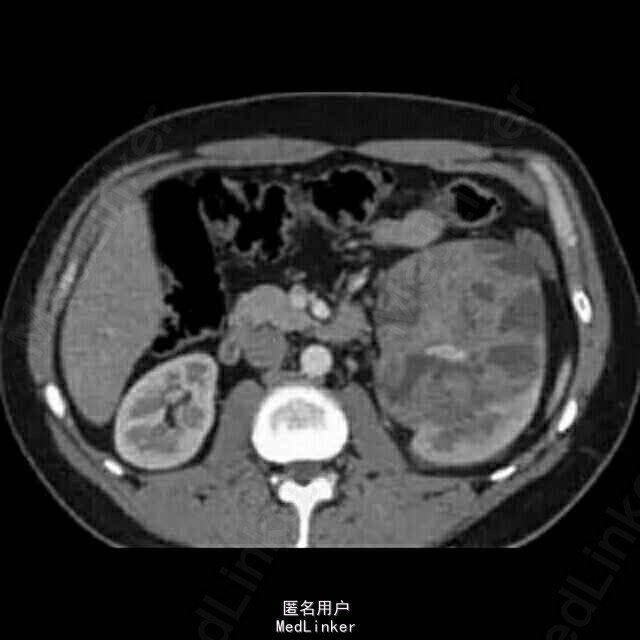

患者为44岁中年男性,因“反复肉眼血尿1月余”入院。 患者1月余前无明显诱因出现肉眼全程血尿,色鲜红,量较多,伴头晕,无尿频、尿急、尿痛,无发热,无腰痛。为求进一步诊治至我院泌尿外科就诊。

入院后完善相关检查,CT提示左肾下极占位,膀胱镜示左输尿管上段、肾盂占位。

考虑“左肾恶性肿瘤”可能性大。遂行肾癌根治术,术中见腹膜后及周围粘连明显。术后病理示:透明细胞癌,8*6*3cm,侵及肾纤维膜,分期PT4N0M0.术后干扰素治疗3个月。1年后因左上腹疼痛伴血尿再次至我院就诊,CT提示腹膜后软组织结节,腹主动脉旁、左侧腰大肌肿物。考虑肿瘤复发转移,遂行腹腔复发灶姑息切除,肿瘤30*20*30cm,术后与索坦治疗后。